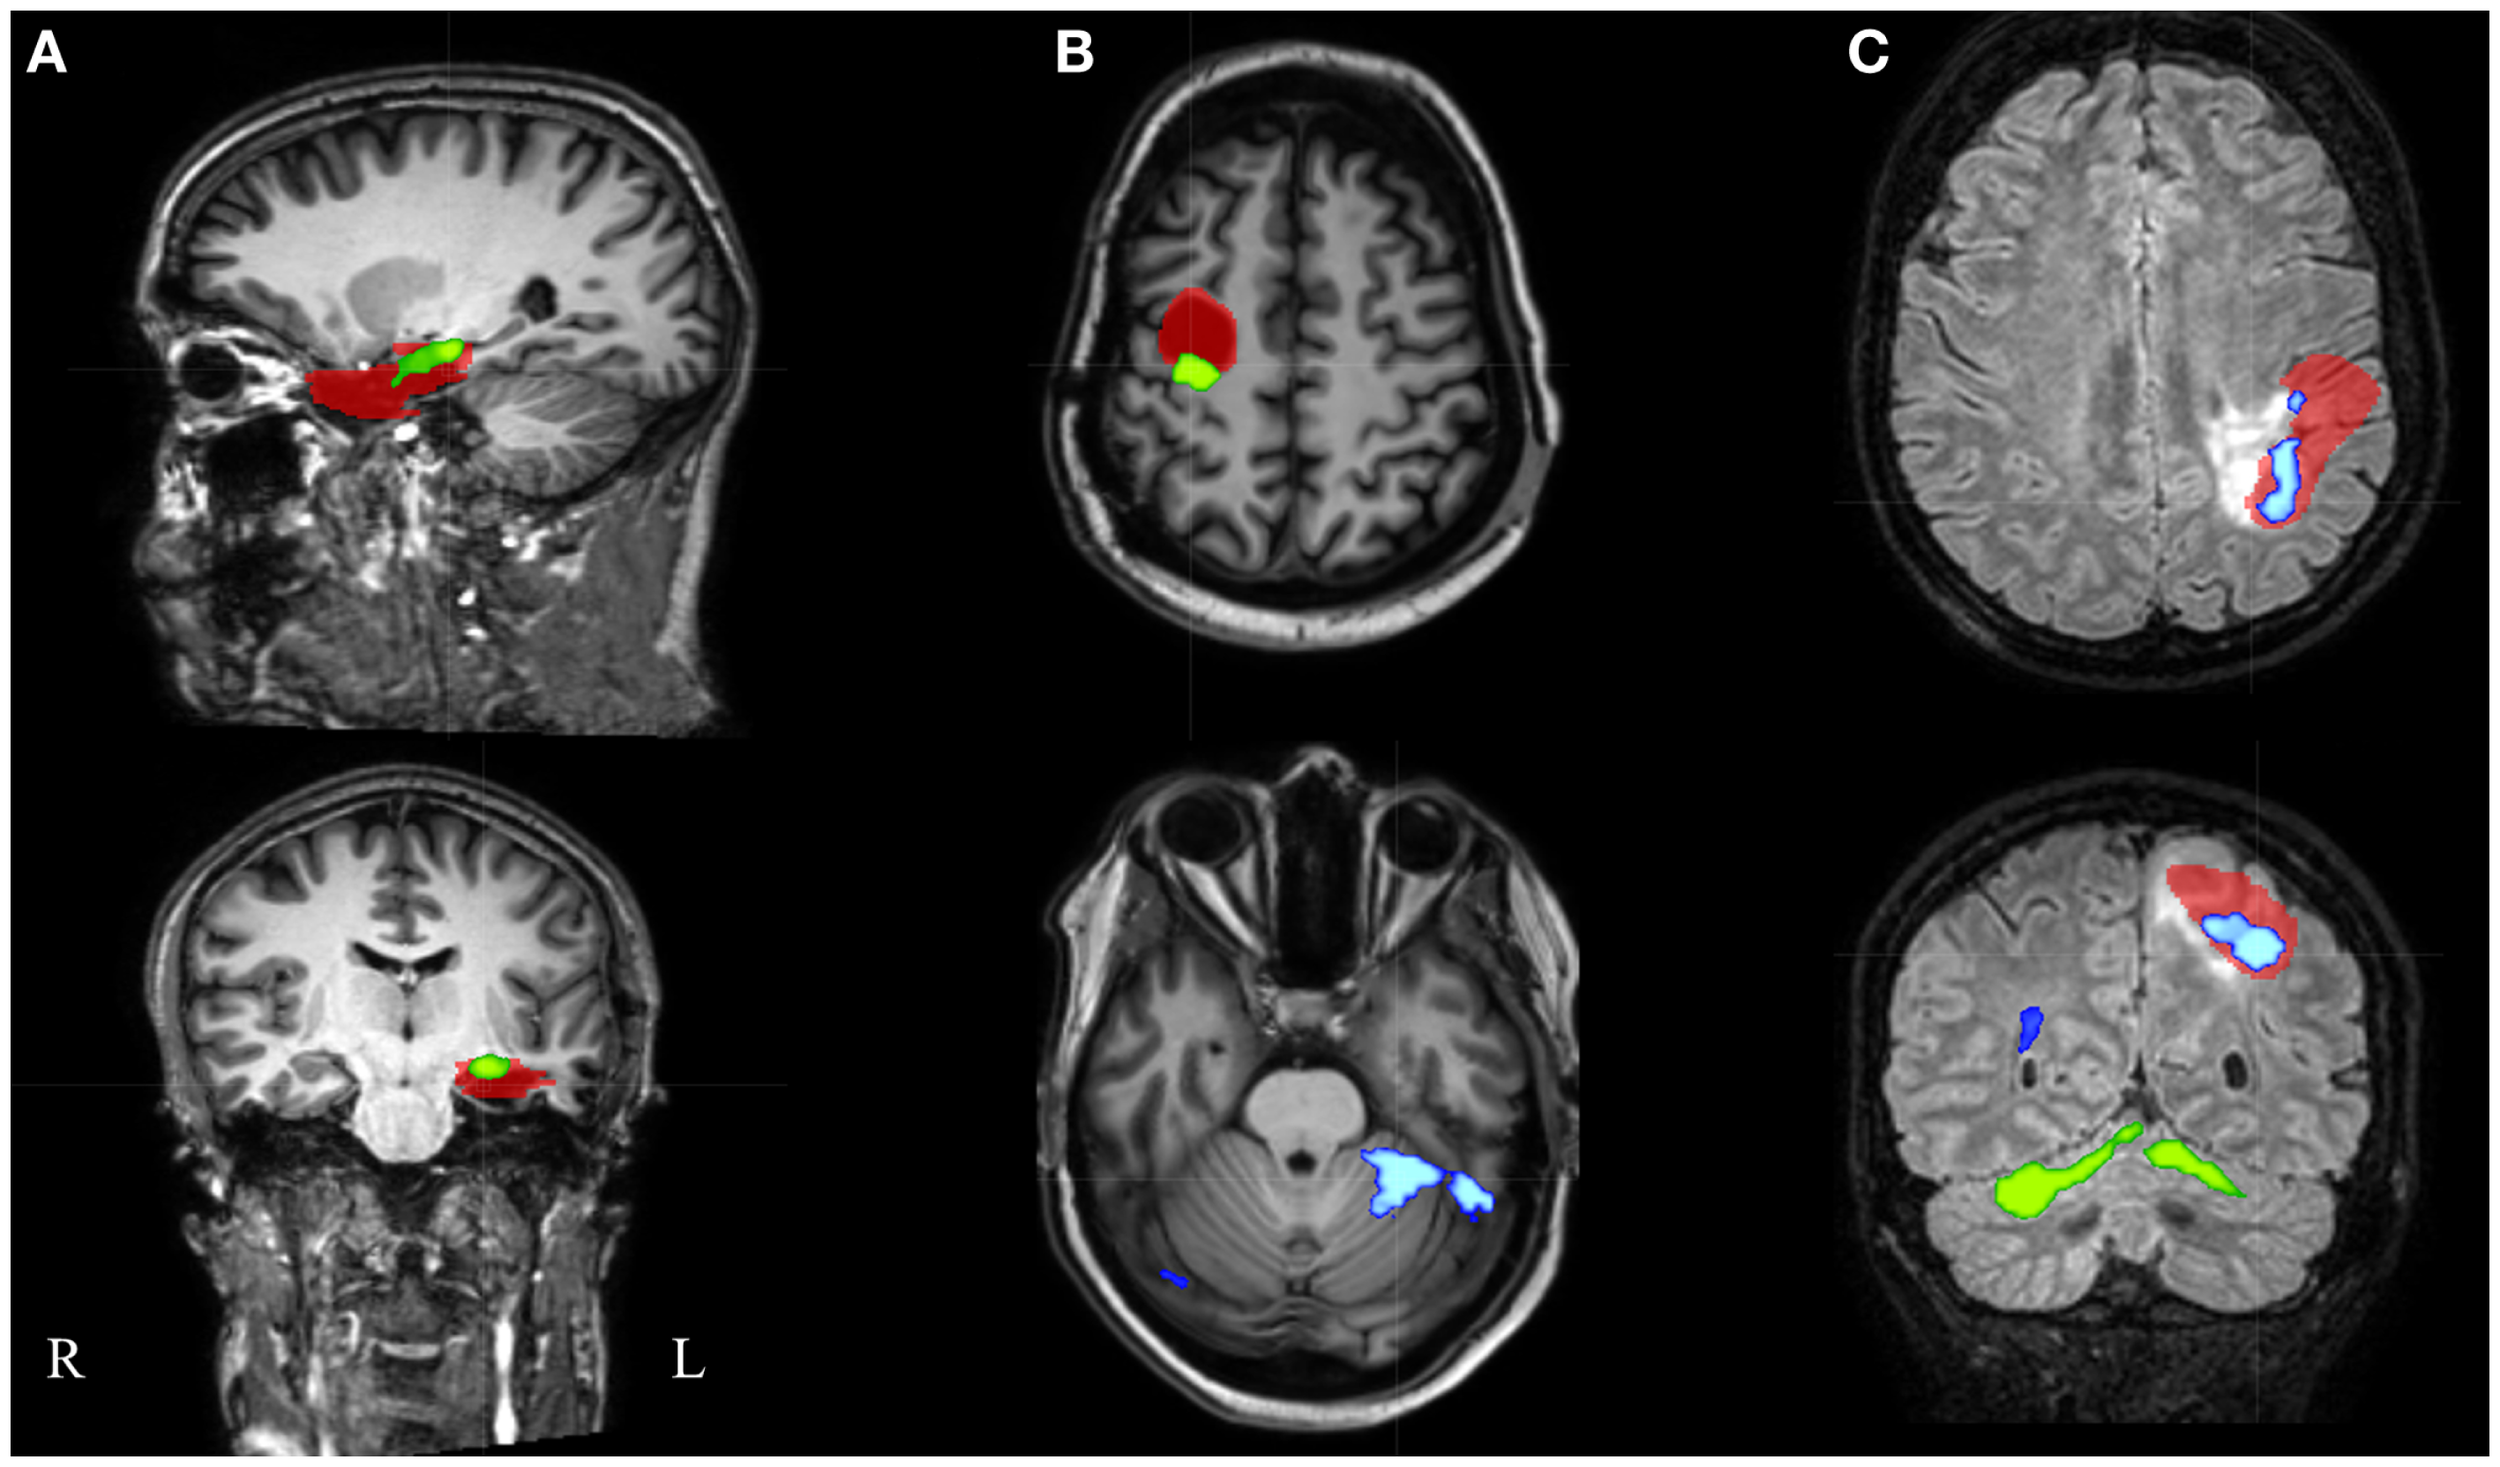

Figure 5

Electroencephalography-functional magnetic resonance imaging results after thresholding at Z = 3.5 at the voxel level combined with a minimal cluster extent of 350 voxels are overlaid on representative slices of the structural MRI in three patients. (A) Patient 16 had only 1 suprathreshold activation. This cluster containing the maximal significant activation (green colored) was localized within the IOZ (red colored). (B) In patient 6, the cluster containing the maximal significant activation (green colored) was overlapping the IOZ, while an additional activation cluster (blue colored) was situated within the contralateral cerebellum. (C) Patient 15 was the only patient with a BOLD activation cluster (blue colored) overlapping the IOZ, which did not contain the maximal significant activation (green colored); R, right; L, left.

In an additional analysis, we looked at the cluster containing the maximal significant BOLD activation. This resulted in similar sensitivity and specificity when using the same minimal cluster extent of 350 voxels (Figure 3). A sensitivity of 57% and a specificity of 100% were obtained for a broad range of Z-score thresholds from 3.2 to 3.5 (green areas in Figure 5). Interestingly, this combination of sensitivity and specificity could also be reached using other settings for minimal cluster size (from 250 voxels up to 600 voxels) but with a smaller range of corresponding Z-score thresholds. By using the cluster containing the maximal significant activation instead of all EEG-fMRI activations, we discarded the additional, non-localizing clusters (blue areas in Figure 4) distant from the IOZ with sacrificing minimal sensitivity (4.8%) at 100% specificity. Only 1 of 21 patients (4.8%) (patient 15) showed a BOLD activation cluster overlapping the IOZ, which did not contain the maximal significant activation (Figure 5).